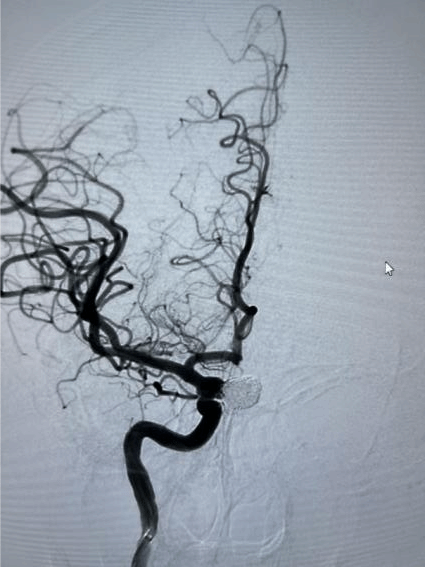

1.经桡动脉脑血管造影术

全脑血管造影能够显示从主动脉弓到颈部、脑部的所有大血管、毛细血管的详细动态图像,从而指导头颈部血管疾病的药物、介入或外科手术治疗。其检查结果优于“磁共振血管成像(MRA)”和“CTA”,是脑血管病变检查的“金标准”。经桡动脉脑血管造影,优于传统的从股动脉入路进行脑血管造影。具有创伤小、时间短、安全性高、并发症少、痛苦小、恢复快等优点。术后患者即可以下床活动。